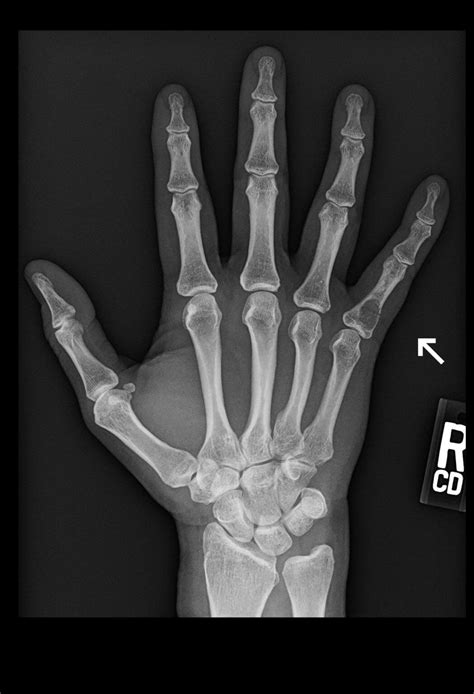

Diagnosing a pinky finger sprain typically involves a physical examination by a healthcare professional. The doctor will assess the range of motion, stability, and any signs of swelling or bruising. In some cases, imaging tests such as X-rays or MRI scans may be ordered to rule out fractures or other injuries.